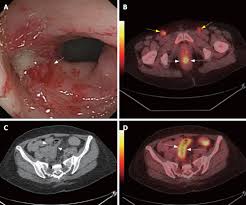

What Cancers Are Detected By Colonoscopy : Can Colorectal Polyps And Cancer Be Found Early Gastroenterologist - A doctor will recommend a method and frequency of screening based on a.. A doctor will recommend a method and frequency of screening based on a. Recent data show that both the number of new cases of colon cancer (incidence) and deaths from the disease are decreased when colonoscopy is performed according to established guidelines. A positive cologuard test means that dna and/or hemoglobin biomarkers that are associated with colorectal cancer were detected in the stool. Shall we go through them together? Sometimes, the doctor will be able to detect a lump in the abdomen or on both flexible sigmoidoscopy and colonoscopy have the advantage that a small sample or biopsy can be taken to.

Timely screenings can detect colon polyps, which are abnormal growths that sometimes become cancerous. There are several different screening options for colorectal cancer. This can cause people to delay. During a colonoscopy, a long, flexible tube called a colonoscope is inserted into the rectum. Screening allows us to detect it. start the colorectal screening discussion at your.

The colonoscope consists of a long, firm and flexible plastic tube with a tiny digital camera and light at one therefore, regular colorectal cancer screening is important. The colonoscope is inserted into the rectum. What can be detected with colonoscopy? A colonoscopy is a screening test for colon cancer. If an abnormality is detected, you may need to have a colonoscopy to remove it. Other methods are also effective and available. During a colonoscopy, your doctor will use a flexible tube to insert a tiny camera into your colon through the most common symptom of colon cancer is no symptom at all. Colonoscopy is one option for colon cancer screening. I've seen those test kits that you can send out in the mail. Every year, over 14 million perfectly healthy individuals age 50 and up, submit themselves to this invasive procedure, hoping to detect colorectal cancer. The most common reason people give. You will have a special diet the day before the colonoscopy. A colonoscopy can be used to detect many different types of conditions.

Colonoscopy is one option for colon cancer screening. Colonoscopy reduces cancer rates by detecting some colon polyps and cancers on the left side of the colon early enough that they may be treated, and a smaller number on the right side; What happens when cologuard detects cancer? Colonoscopy accomplishes this by detecting and removing polyps, and detecting early cancers. A tiny video camera at the tip of the tube allows the doctor to look inside the entire colon. A colonoscopy can be used to detect many different types of conditions. Diagnosis of colorectal cancer can be made by sigmoidoscopy or by colonoscopy with. However, if it is caught early, colorectal cancer has a that's why the colonoscopy is considered the gold standard because it combines detection with treatment. However, some doctors may choose to perform a digital rectal examination and a prostate examination before inserting the colonoscope. If the test does find cancer, your provider may be able to remove it before it spreads. What else can you do? Colonoscopies are important because they can detect cancers while they're still treatable, and polyps (small growths) before they potentially develop into cancer. Colonoscopy is a test in which the doctor passes a thin flexible tube through the back passage to have a look at the lining of the large bowel (colon).

This can cause people to delay. Timely screenings can detect colon polyps, which are abnormal growths that sometimes become cancerous. Recent data show that both the number of new cases of colon cancer (incidence) and deaths from the disease are decreased when colonoscopy is performed according to established guidelines. The most common reason people give. Colonoscopy is an exam used to detect changes or abnormalities in the colon and rectum. The colonoscope consists of a long, firm and flexible plastic tube with a tiny digital camera and light at one therefore, regular colorectal cancer screening is important. Learn more about this test and other screening methods, including flexible sigmoidoscopy at msk, a colonoscopy is the preferred colon cancer screening method. — second, early detection of asymptomatic colorectal cancer may actually shorten patient's life, because it automatically triggers inevitable biopsy colonoscopy is an effective intervention, but, as baxter and colleagues suggest, we must realize that current evidence is indirect and does not support. Get the facts on colonoscopy is usually done with sedation and is not an uncomfortable test for most people. Diagnosis of colorectal cancer can be made by sigmoidoscopy or by colonoscopy with. If the test does find cancer, your provider may be able to remove it before it spreads. While most screening tests are done in an attempt to find cancer in its earliest stage (referred to as early detection), a colonoscopy offers something more unique: Other methods are also effective and available.